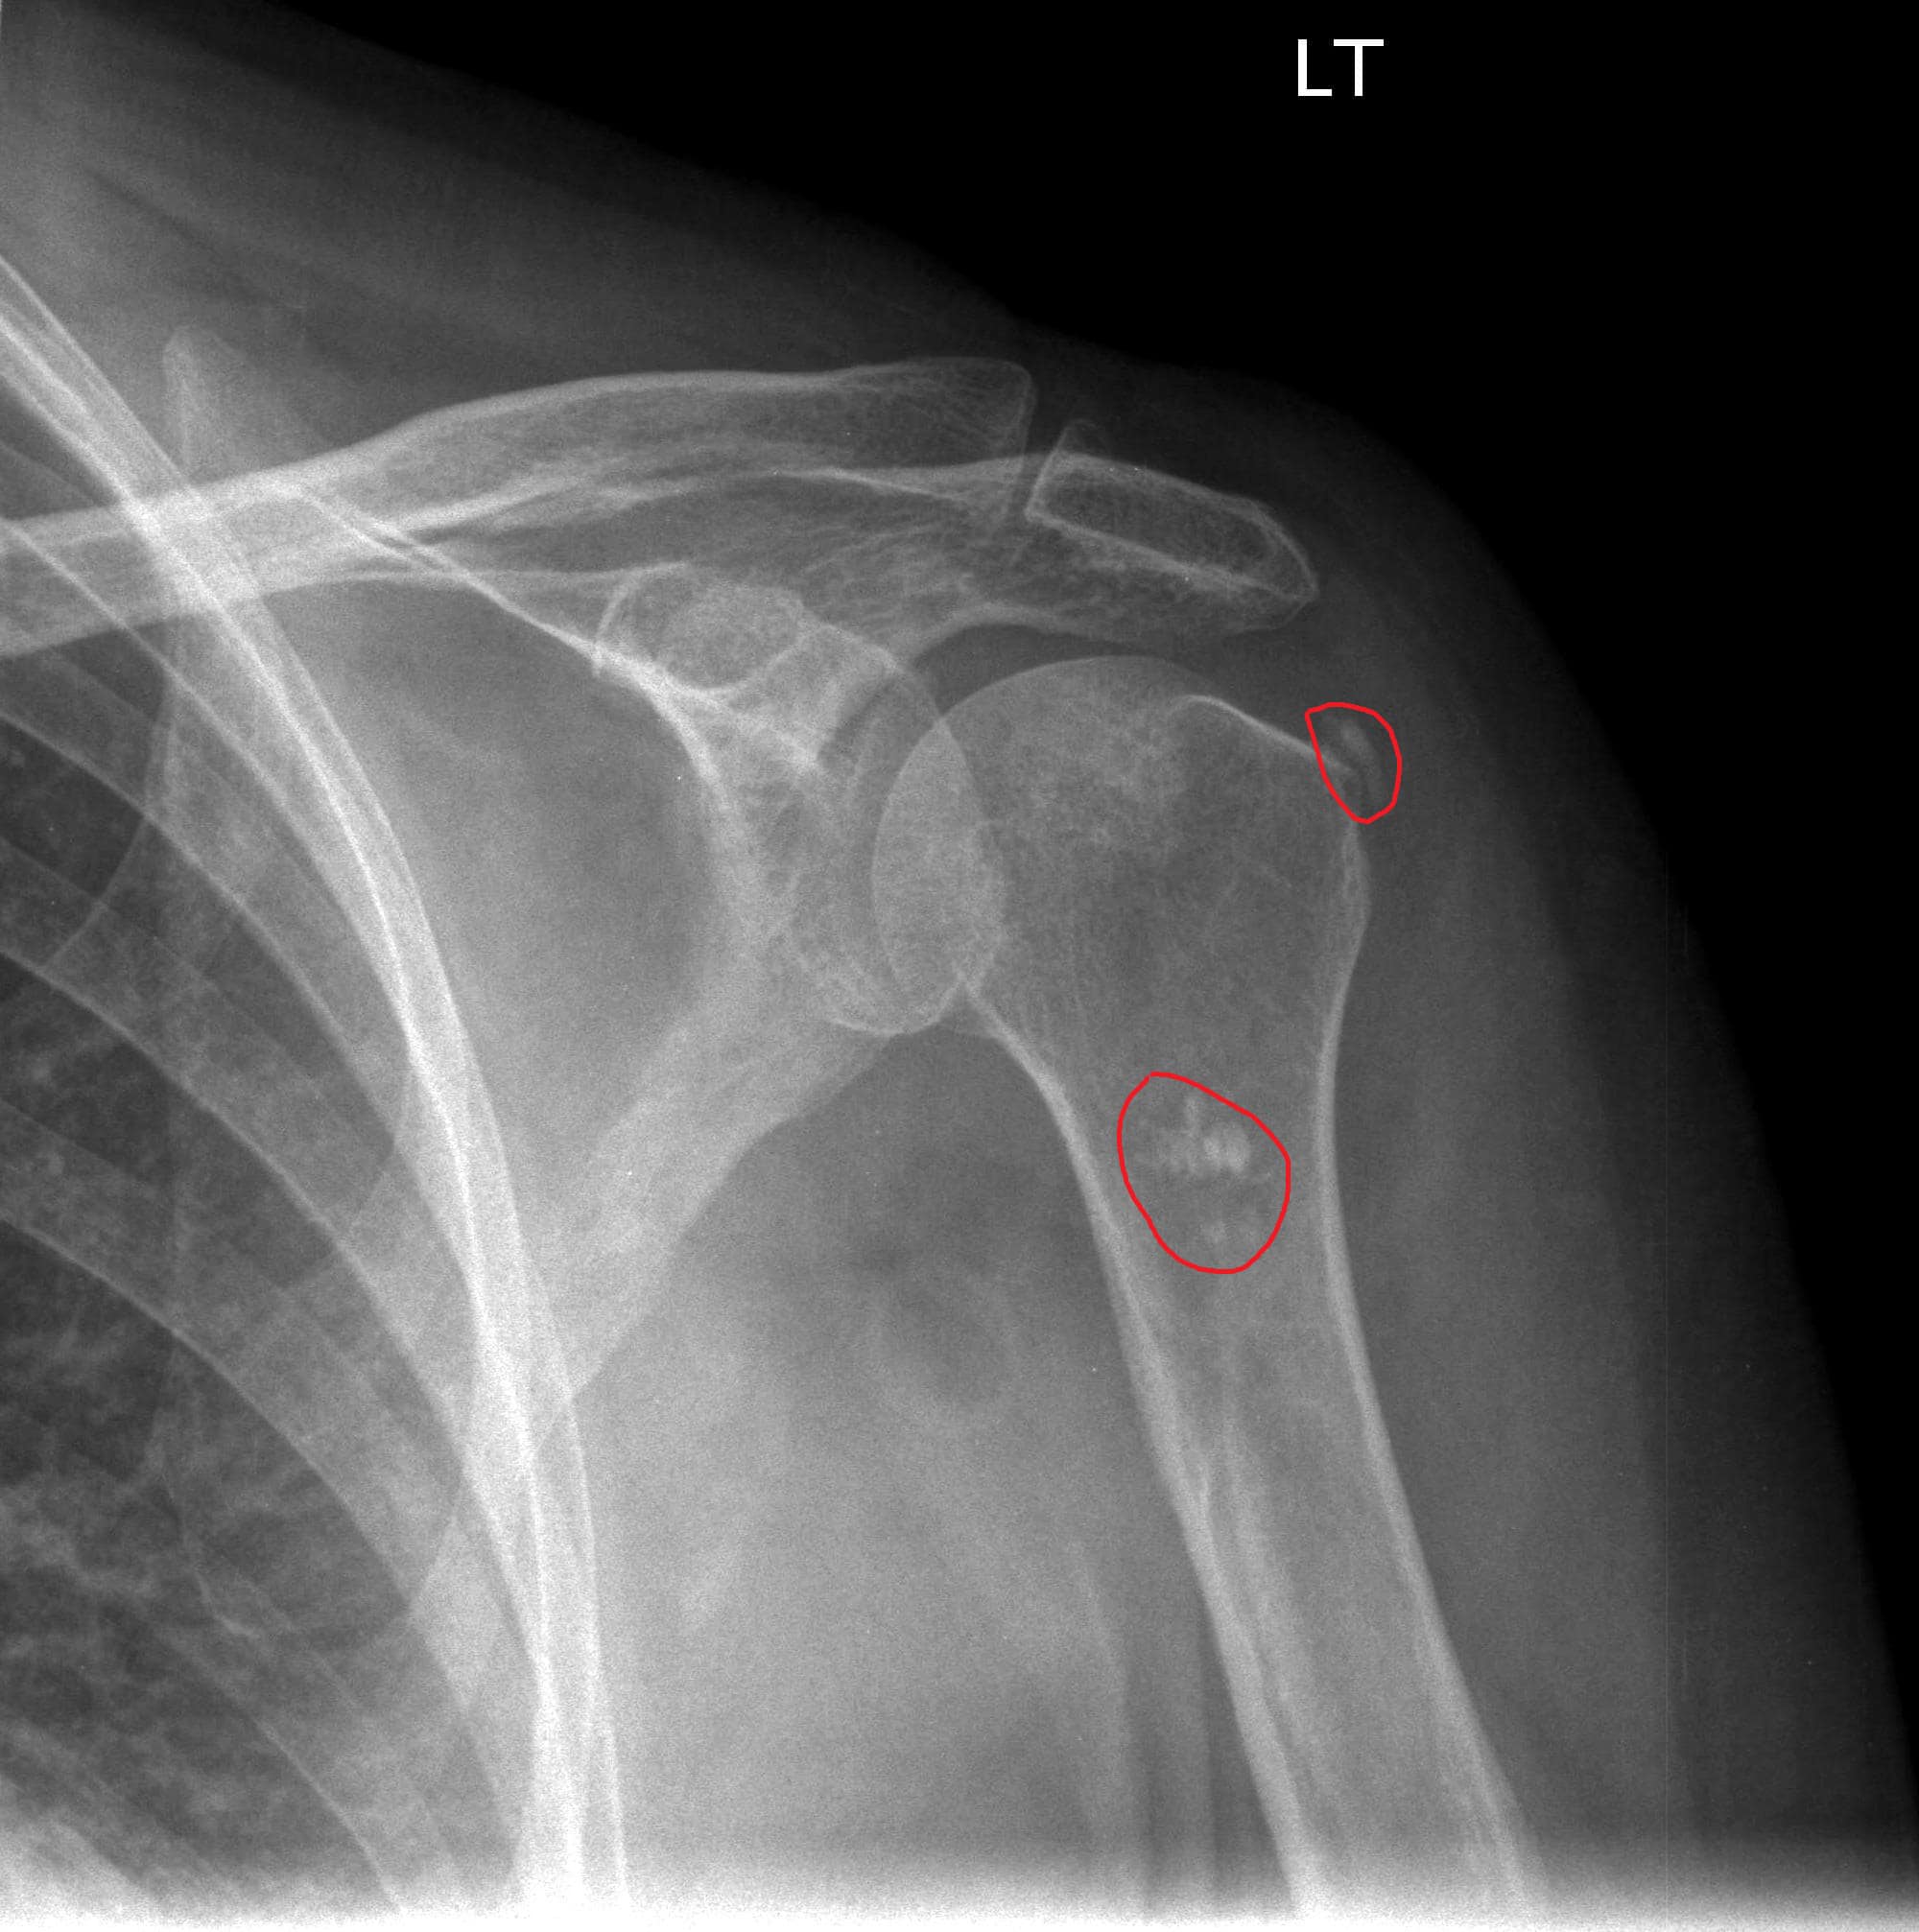

Urgent Care For Shoulder Pain. He feels that he may have “slept on it wrong.” there is no history of trauma. The shoulder joint is a ball and socket joint, think of it as a golf ball sitting on a golf tee.

He feels that he may have “slept on it wrong.” there is no history of trauma. Initial evaluation is aimed at ruling out visceral or neck cause and then identifying the shoulder structure component responsible for pain. It allows for a large amount of motion, so supporting muscles and tendons are a.

I broke my nose, and everything from signing in, to seeing the nurse and pa, was streamlined and i am grateful for and impressed with the level of care they provided. Rotator cuff tears (partial or full thickness) various types of arthritis (bone on bone) biceps tendinosis, avulsion, or dislocation; Even if it turns out that the pain isn’t attributed to a coronary issue, it’s better to be safe than sorry.